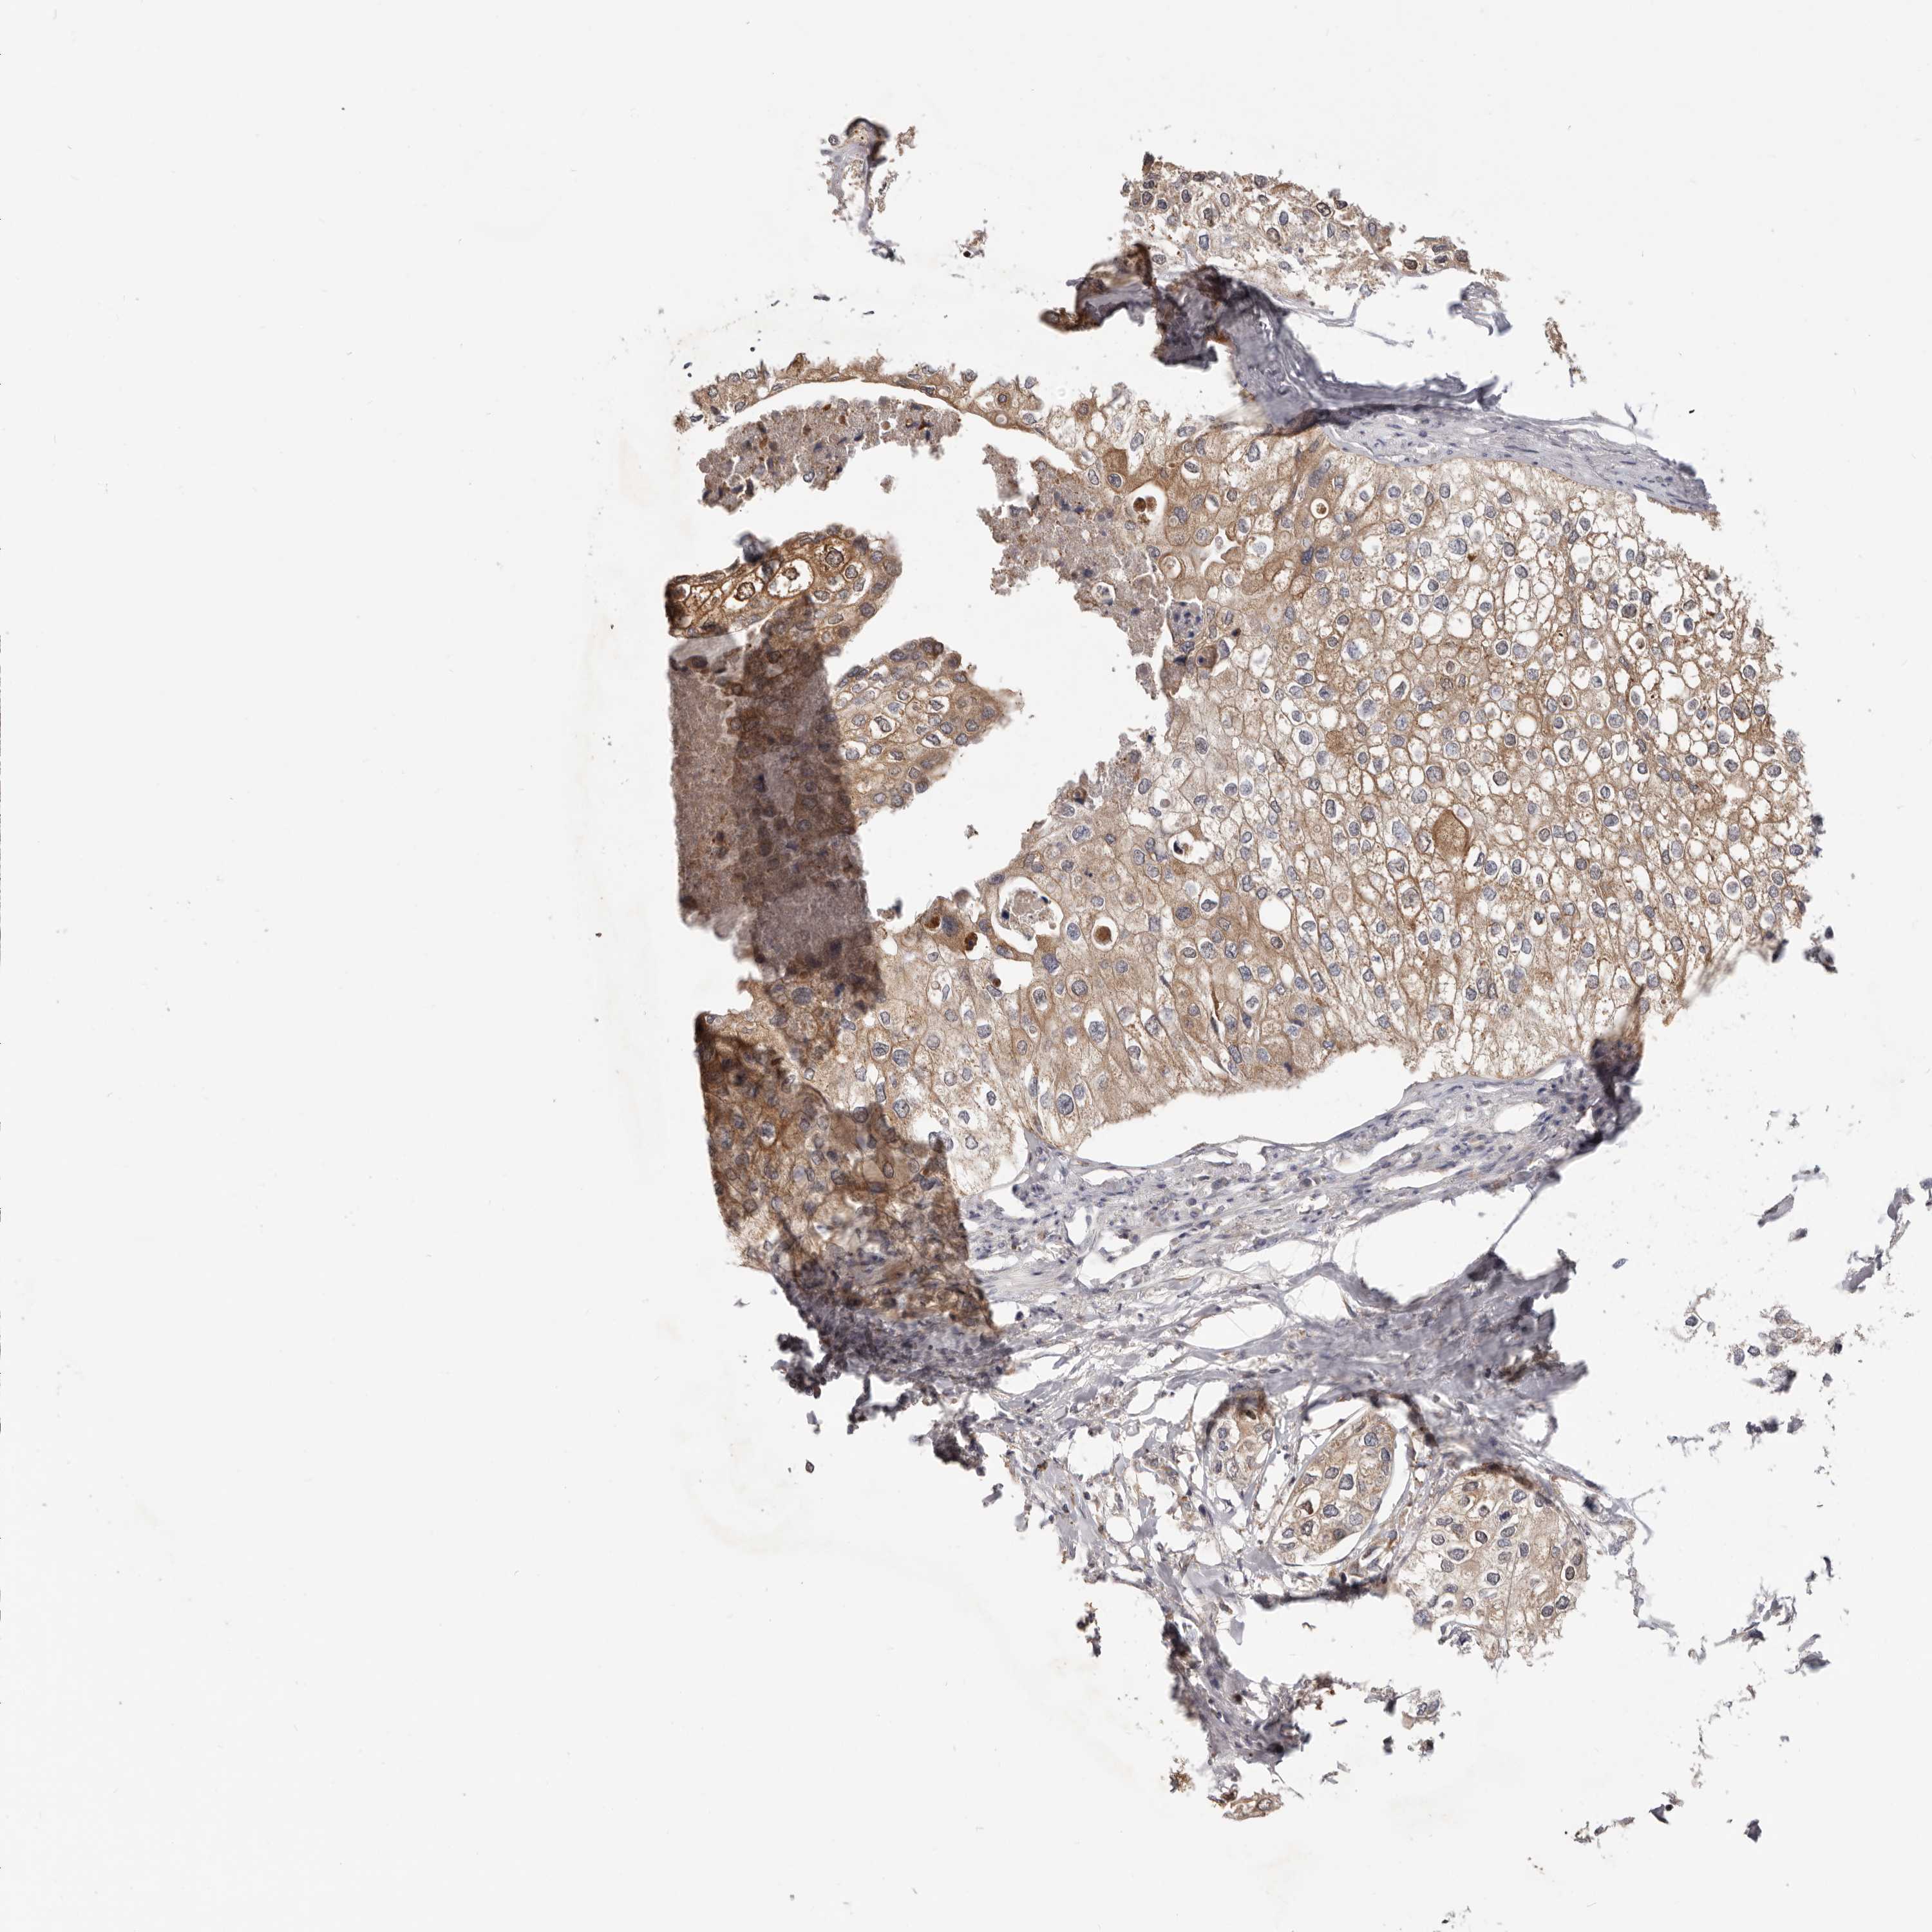

UROTHELIAL CANCER - Protein expressioni

A mouse-over function shows sample information and annotation data. Click on an image to view it in a full screen mode. Samples can be filtered based on level of antibody staining by selecting one or several of the following categories: high, medium, low and not detected. The assay and annotation is described here.

Antibody stainingi

Antibody staining in the annotated cell types in the current human tissue is reported as not detected, low, medium, or high, based on conventional immunohistochemistry profiling in selected tissues. This score is based on the combination of the staining intensity and fraction of stained cells.

Each image is clickable and will lead to virtual microscopy that enables deeper exploration of all samples and also displays staining intensity scores, fraction scores and subcellular localization as well as patient and tissue information for each sample.

Antibody HPA029925

Antibody CAB004490

Urothelial carcinoma, Low grade

Urothelial carcinoma, High grade